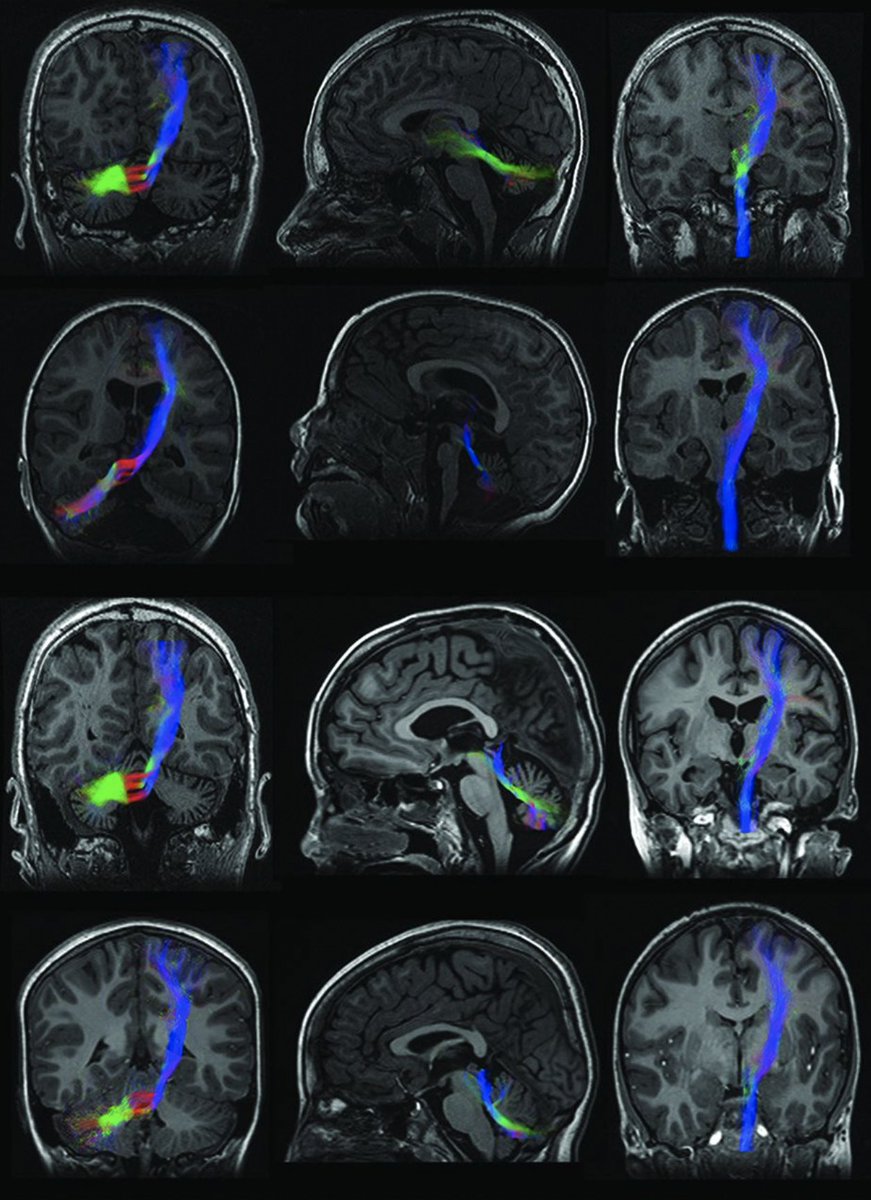

If you correctly answered first question, congrats! Here’s your second chance if you didn’t. If we divide the images BELOW⬇️ in 3 columns, column 1, 2 and 3 from left to right, which column you think will provide the answer of the above question?

So there it is- Cortico-ponto-cerebellar (CPC) pathway.

The cerebellum has a significant input from the cerebral hemispheres, the bulk of which is contained in the CPC pathway. The densest cortico-ponto-cerebellar projections arise from the precentral and prefrontal cortical areas-22473241

Other cerebro-cerebellar connections are relayed through the inferior olive and reticular formation.